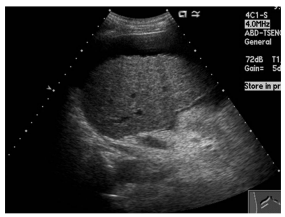

58.下圖之超音波影像中,編號45的區域屬於下列何種假影? (A)acoustic shadow (B)distal acoustic enhancement (C)comet tail artifact (D)section-thickness artifact

68.下圖之超音波影像中,最可能的診斷為下列何者? (A)肝硬化 (B)急性肝炎 (C)局部結節性增生 (D)脂肪肝